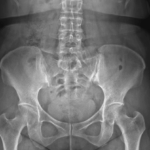

[doctormodu]3 SI joint arthritis

03 천장관절 증후군 SI joint syndrome